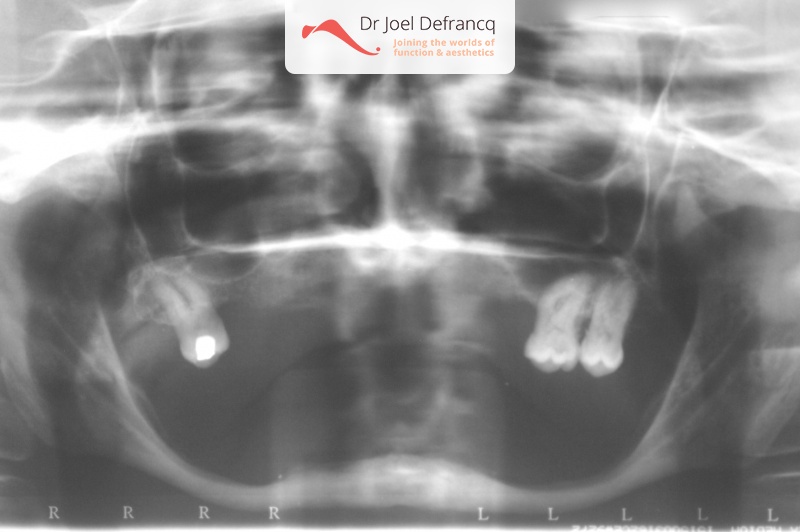

Daphne: from extreme atrophic to fixed teeth on implants

Behandeling tandheelkundige implantaten

- Implantaten met beenopbouw